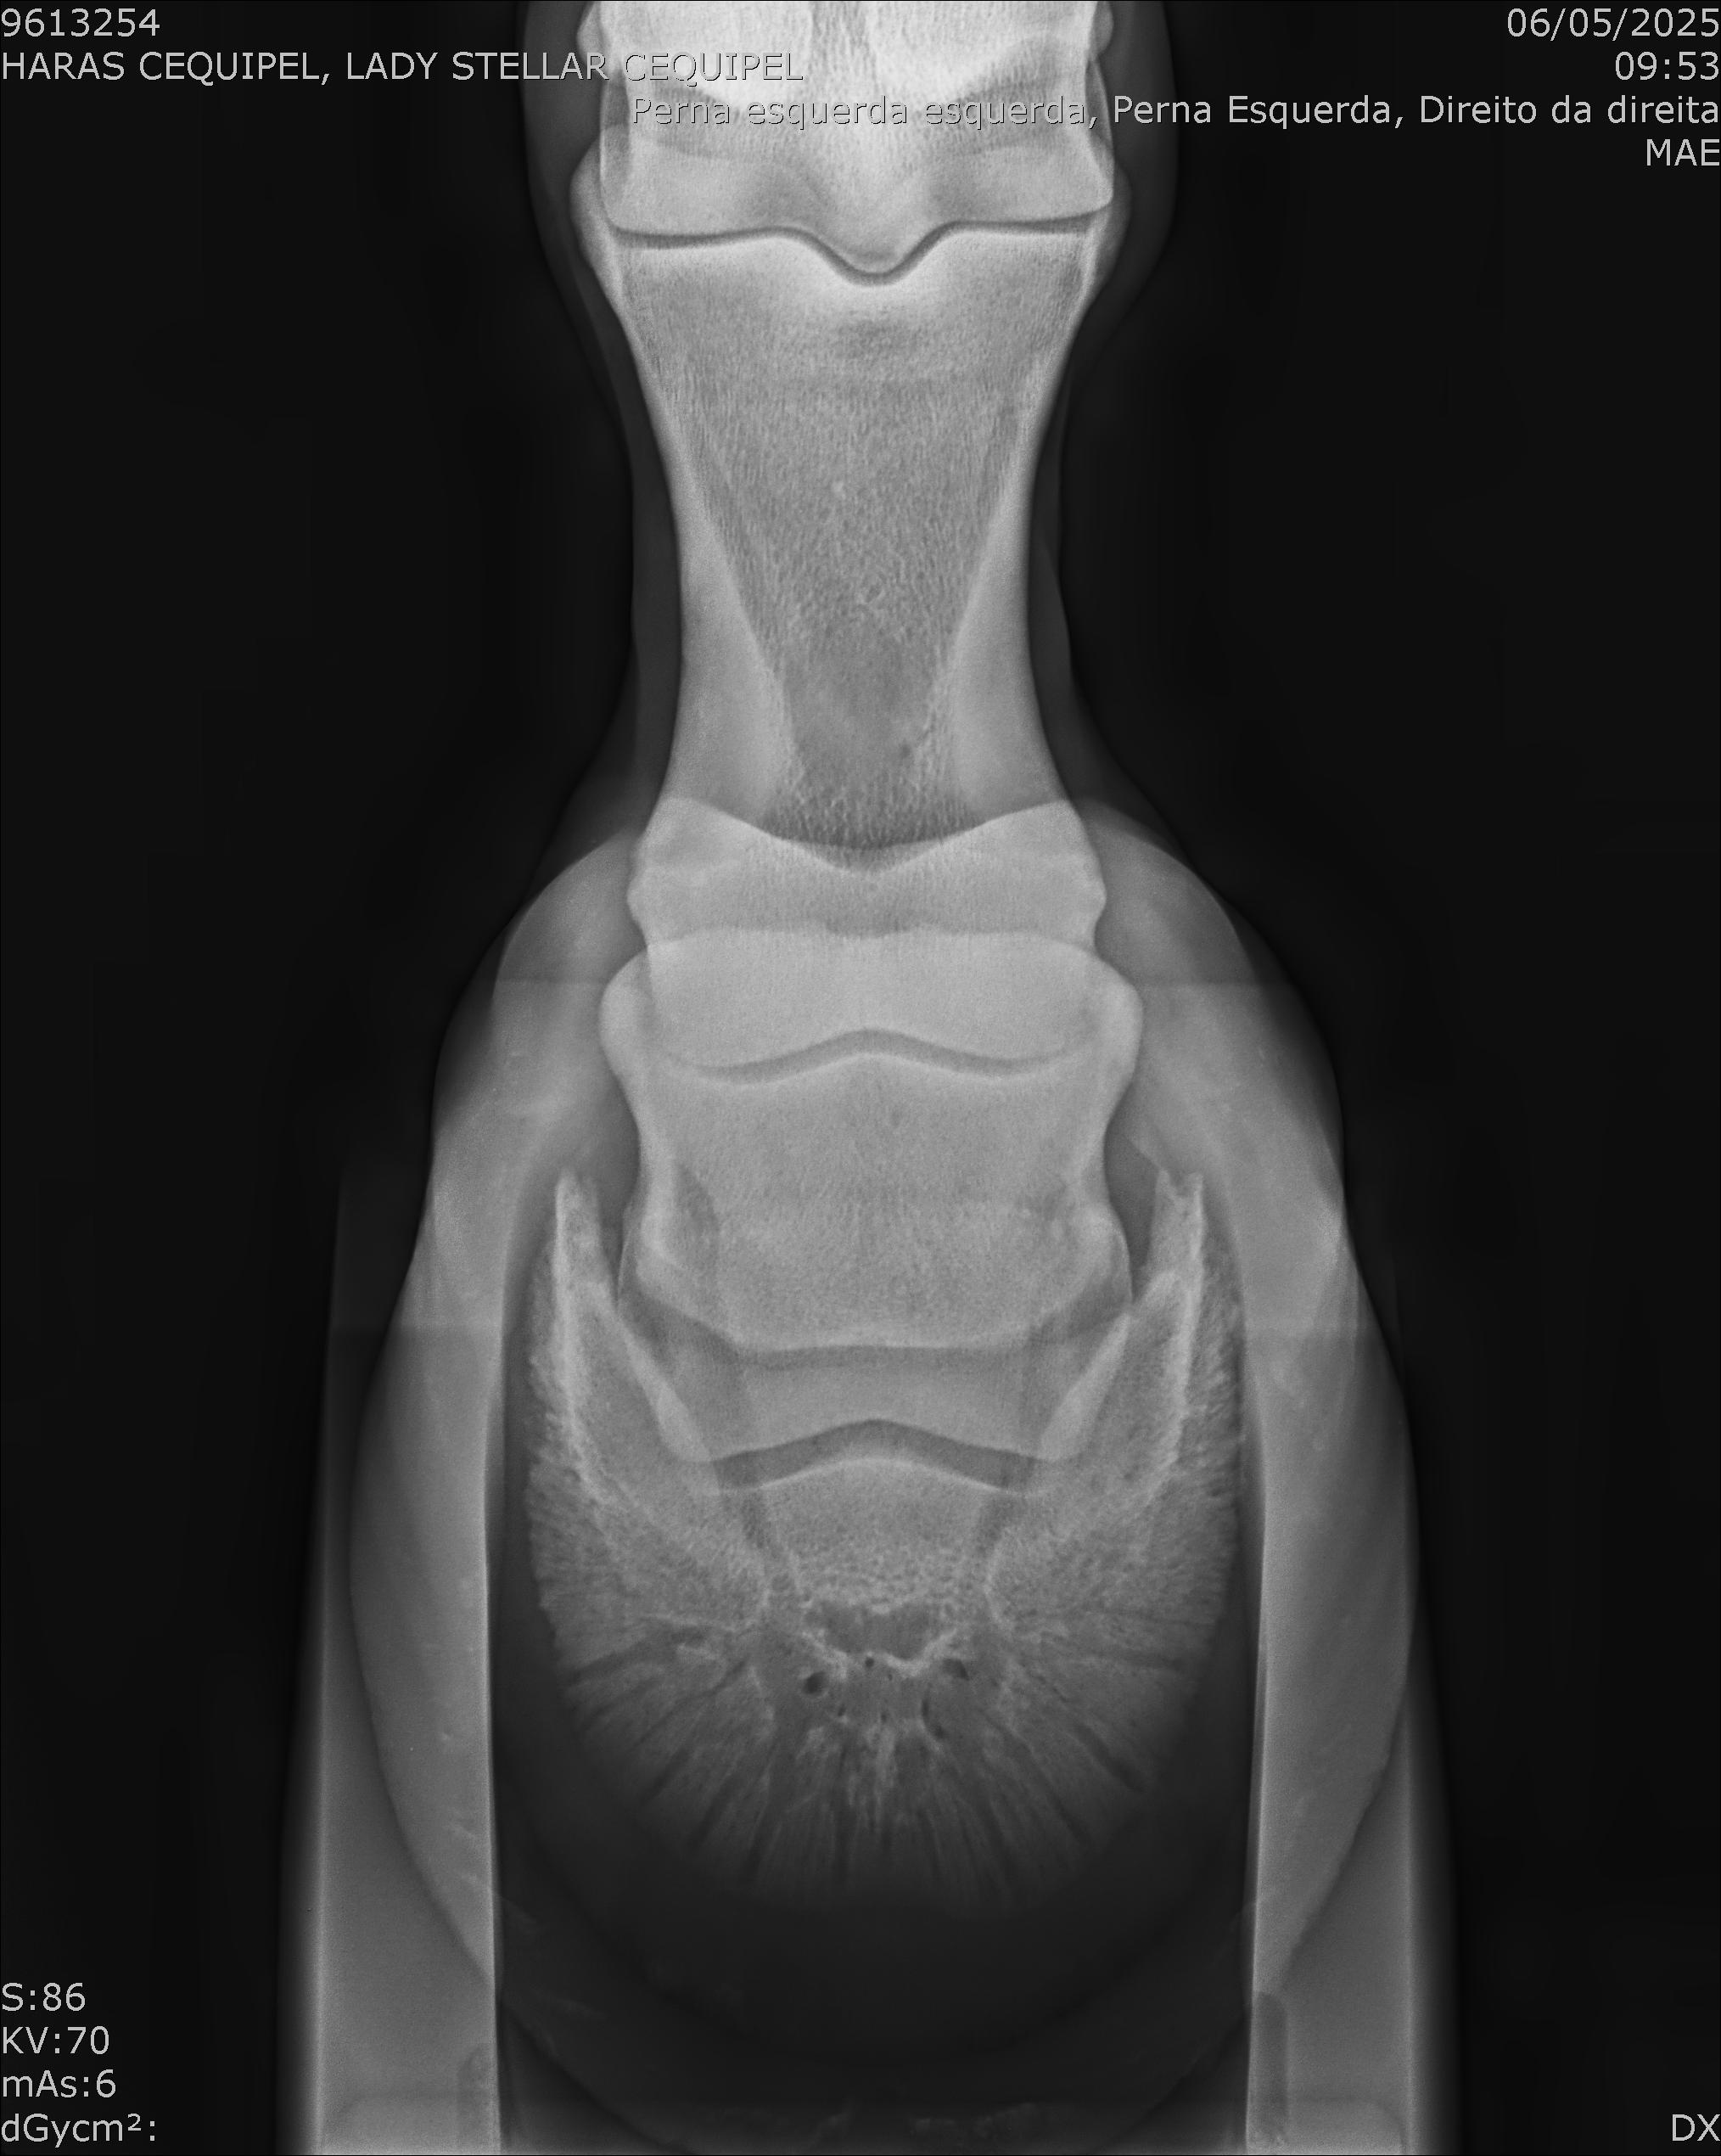

:: RAIOS-X DO LOTE